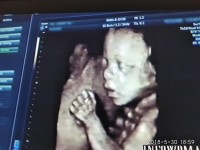

«Κανένα μυστικό δεν έχουν πλέον οι εκφράσεις του εμβρύου στη μήτρα, μιας και υπάρχει ο τετραδιάστατος υπέρηχος, που αποτυπώνει πιστά κινήσεις, εκφράσεις, χαρακτηριστικά του προσώπου αλλά κυρίως την ανατομία προσώπου, σώματος και άνω και κάτω άκρων».Αυτό υπογραμμίζει ο Μαιευτήρας, Χειρουργός-Γυναικολόγος Δρ. Νικόλαος Σκαρτάδος, αναφορικά με τις δυνατότητες που έχει η τετραδιάστατη απεικόνιση, όχι φυσικά μόνο για τα …φωτογραφικά ενσταντανέ και την καταγραφή του φύλου, αλλά κύρια για τα σοβαρά απεικονιστικά οφέλη που έχει για τη συνολική υγεία του κυοφορούμενου εμβρύου.

Όσο ελκυστική όμως και αν είναι η «φωτογραφική» απεικόνιση του εμβρύου και η τρυφερότητα που κινητοποιεί στους υποψήφιους γονείς, για τους γυναικολόγους είναι ιδιαίτερα σημαντική η λειτουργία της καρδιάς και των αγγείων που «αποκαλύπτονται» στις δυνατότητες του 4d υπερήχου, δίνοντας «όπλα» έγκαιρης διάγνωσης για οποιοδήποτε πρόβλημα προκύψει, έτσι ώστε πλέον να έρχονται στο φως με πληρότητα οι όποιες ανατομικές βλάβες εμφανίζει η ενδομήτρια ζωή του εμβρύου.